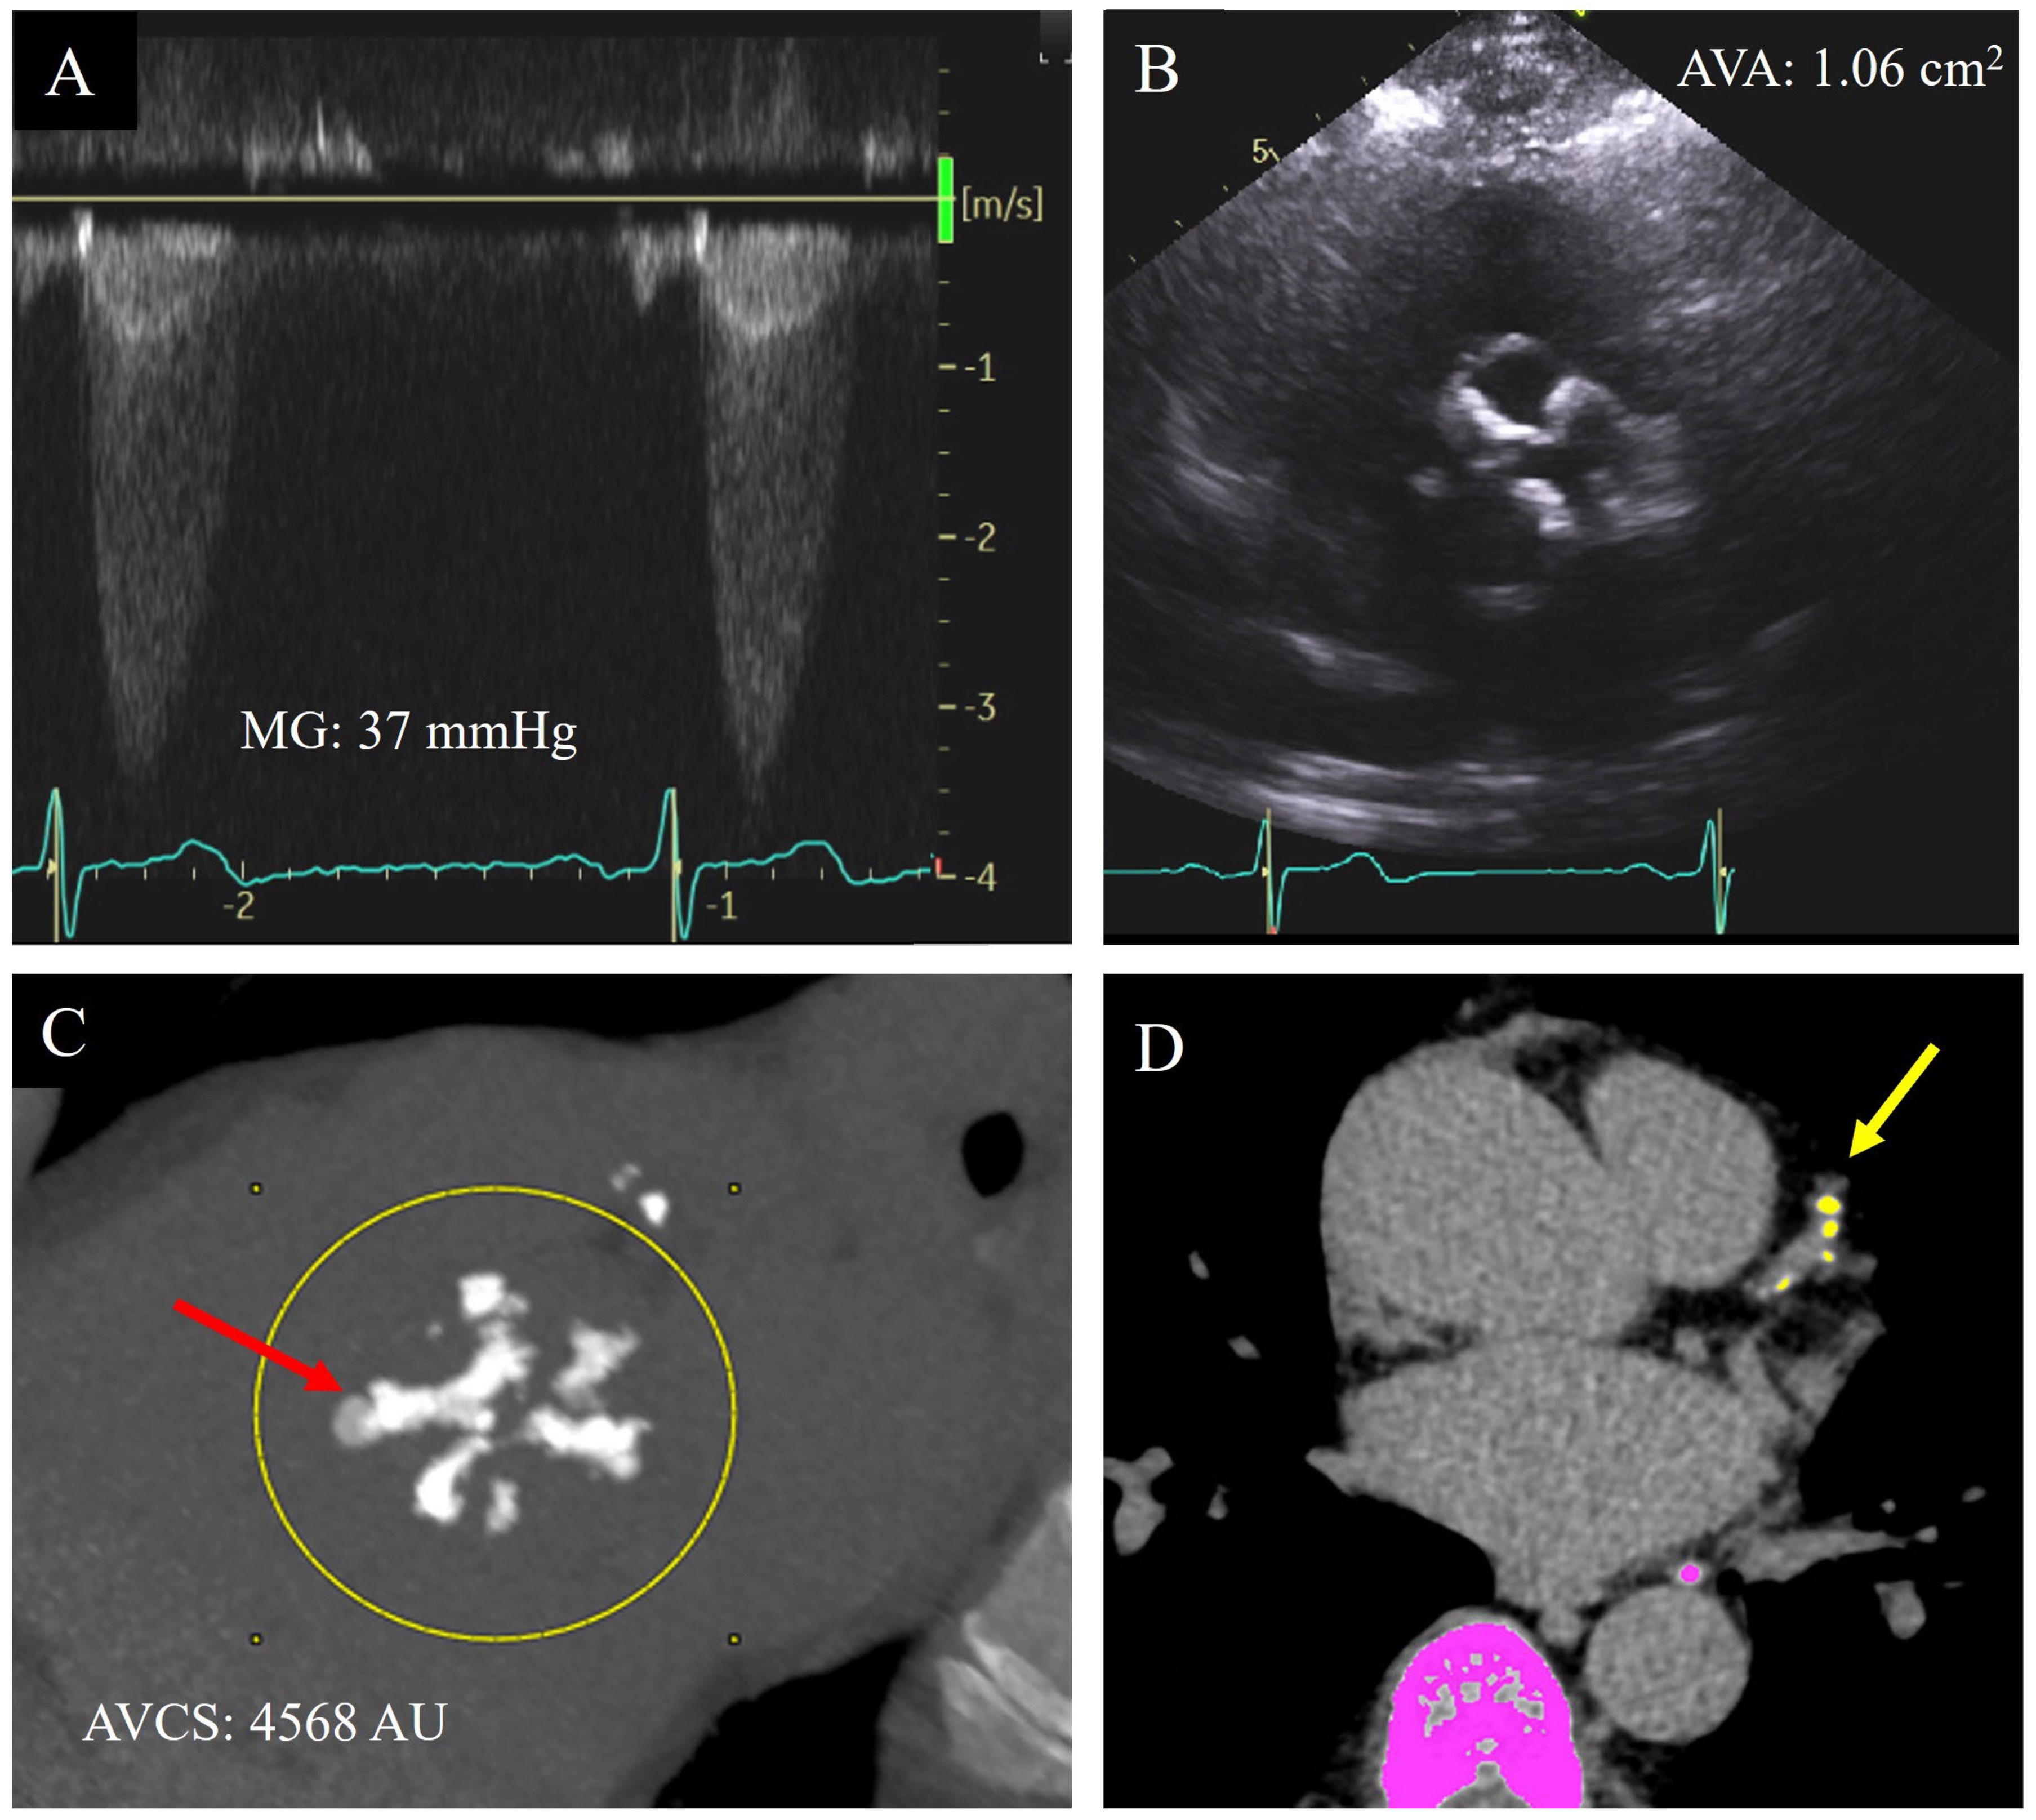

There is diagnostic certainty when all quantitative echocardiographic parameters are aligned in either the moderate or severe AS range, corresponding with the visual appearance on 2D echocardiography of limitation of cusp excursion, and match with the presence or absence of symptomology [13]. Differentiation between moderate and severe AS is critical in decision-making for aortic valve replacement. However, this is often complicated in a significant proportion of cases due to discordance between quantitative TTE measurements or with the patient’s symptoms. [11] (Figure 2A,B).

Figure 2.

A 69-year-old male with bicuspid aortic valve and shortness of breath on exertion only at high elevations. He had discordant echocardiographic parameters for severity of aortic stenosis, with a clinical echocardiogram report noting overall moderate–severe aortic valve stenosis: systolic mean Doppler gradient (MG) 37 mmHg (A), aortic valve area (AVA) by Doppler 1.06 cm2 (B), dimensionless index 0.23, and normal indexed stroke volume (58 mL/m2). He proceeded to have an aortic valve calcium score (AVCS) by cardiac computed tomography ((C), red arrow) which demonstrated a score of 4568 AU, reclassifying aortic valve stenosis as severe. This scan also demonstrated calcification in the left anterior descending coronary artery ((D), yellow arrow).

Given the overlap in risk factors for the incidence of AV calcification and CAC, detection of AV calcification may be a marker of coronary artery disease (CAD) (Figure 2D). Studies have found AV calcification to be a marker of subclinical CAD, with a degree of CAD being detected in up to 70% of patients with severe AS [4,58]. Furthermore, the presence of AV calcification is not only associated with a positive CAC score but also correlated with the severity of CAD. Significantly, AVCS has been identified as independent of cardiovascular risk factor for CAD [46].